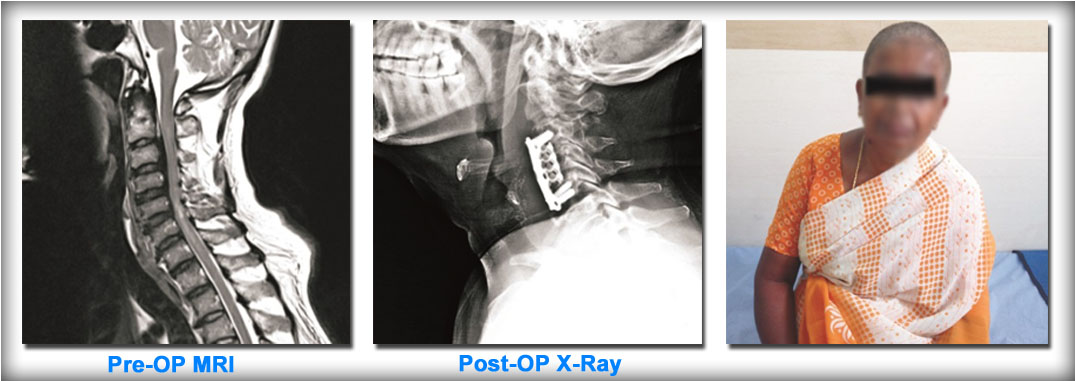

CERVICAL MYELOPATHY:

Cervical myelopathy is a condition where the patient develops weakness of both upper and lower limbs with unsteady gait due to compression of cervical spinal cord. This patient a 55yr old female was operated for cervical myelopathy (cervical corpectomy and cage fixation) and gradually improved and was able to do her day to day activities in 5 months’ time.

Case Example: